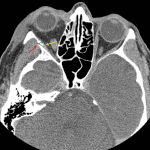

- Acute right zygomaticomaxillary complex fracture with nondisplaced fracture of the zygomatic arch, mildly displaced fractures of the zygomatic and frontal bones near the zygomaticofrontal suture, mildly displaced fractures of the lateral and inferior orbital walls, and mildly displaced fractures of the anterior, posterior, and medial walls of the maxillary sinus. The orbital floor fracture involves the infraorbital foramen

- Small lateral retrobulbar, extraconal hematoma with right proptosis

Acute right zygomaticomaxillary complex (ZMC) fracture with nondisplaced fracture of the zygomatic arch, mildly displaced fractures of the zygomatic and frontal bones near the zygomaticofrontal suture, mildly displaced fractures of the lateral and inferior orbital walls, and mildly displaced fractures of the anterior, posterior, and medial walls of the maxillary sinus. The orbital floor fracture involves the infraorbital foramen.

Small lateral retrobulbar, extraconal hematoma with right proptosis. No imaging evidence of extraocular muscle entrapment. Globes are intact.